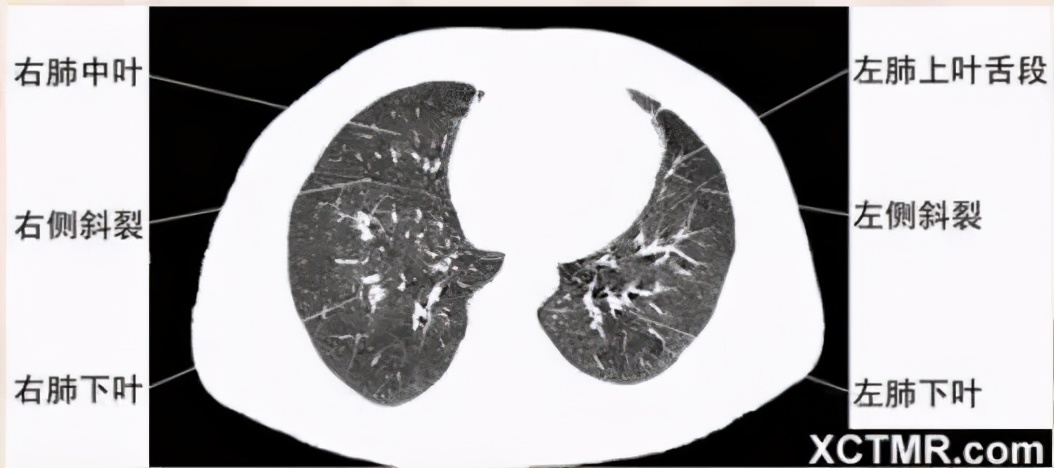

肺段划分